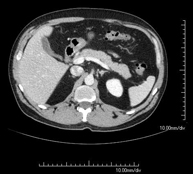

- Abdominal and pelvic CT

Diagnostic test that consists of obtaining high-definition anatomical images (bone structures, vascular structures, liver, pancreas, gallbladder, kidneys, adrenal glands, spleen, small and large intestine, bladder, uterus and ovaries, prostate and seminal vesicles, ureters, etc.) using CT (computed tomography) equipment. Most studies require the use of iodinated contrast.